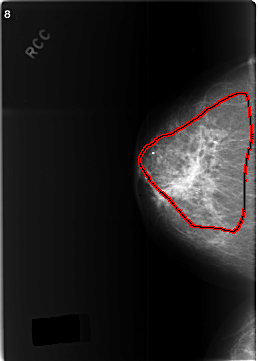

Volume: cancer_09 Case: C-0342-1

C_0342_1.RIGHT_CC

RIGHT_CC LINES 5768 PIXELS_PER_LINE 4120 BITS_PER_PIXEL 12 RESOLUTION 50 OVERLAY

FILE: C_0342_1.RIGHT_CC.OVERLAY

TOTAL_ABNORMALITIES 1

ABNORMALITY 1

LESION_TYPE MASS SHAPE ASYMMETRIC_BREAST_TISSUE MARGINS ILL_DEFINED

ASSESSMENT 5

SUBTLETY 5

PATHOLOGY MALIGNANT

TOTAL_OUTLINES 1

BOUNDARY